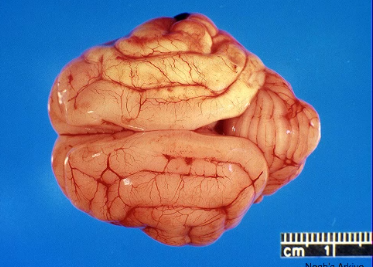

what is this?

bacterial meningitis of neonates